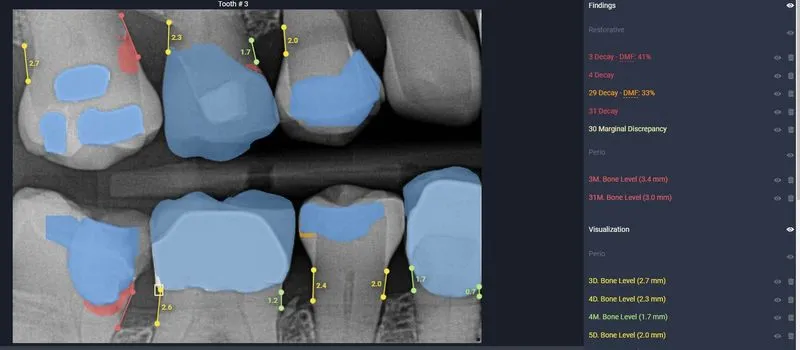

AI activated, showing Decay in red, and Yellow lines indicate bone loss

Not only does our AI serve as your trusted dental confidant, offering a secondary assessment that's as reliable as your favorite dental hygienist, but it's also the go-to tool for insurance companies to verify the quality of your X-rays. But wait, there's more! Our AI isn't just a one-trick pony. It possesses the prowess to spot decay, detect infections, measure bone density for signs of bone loss, identify tartar buildup, and flag any abnormalities that warrant further inspection.